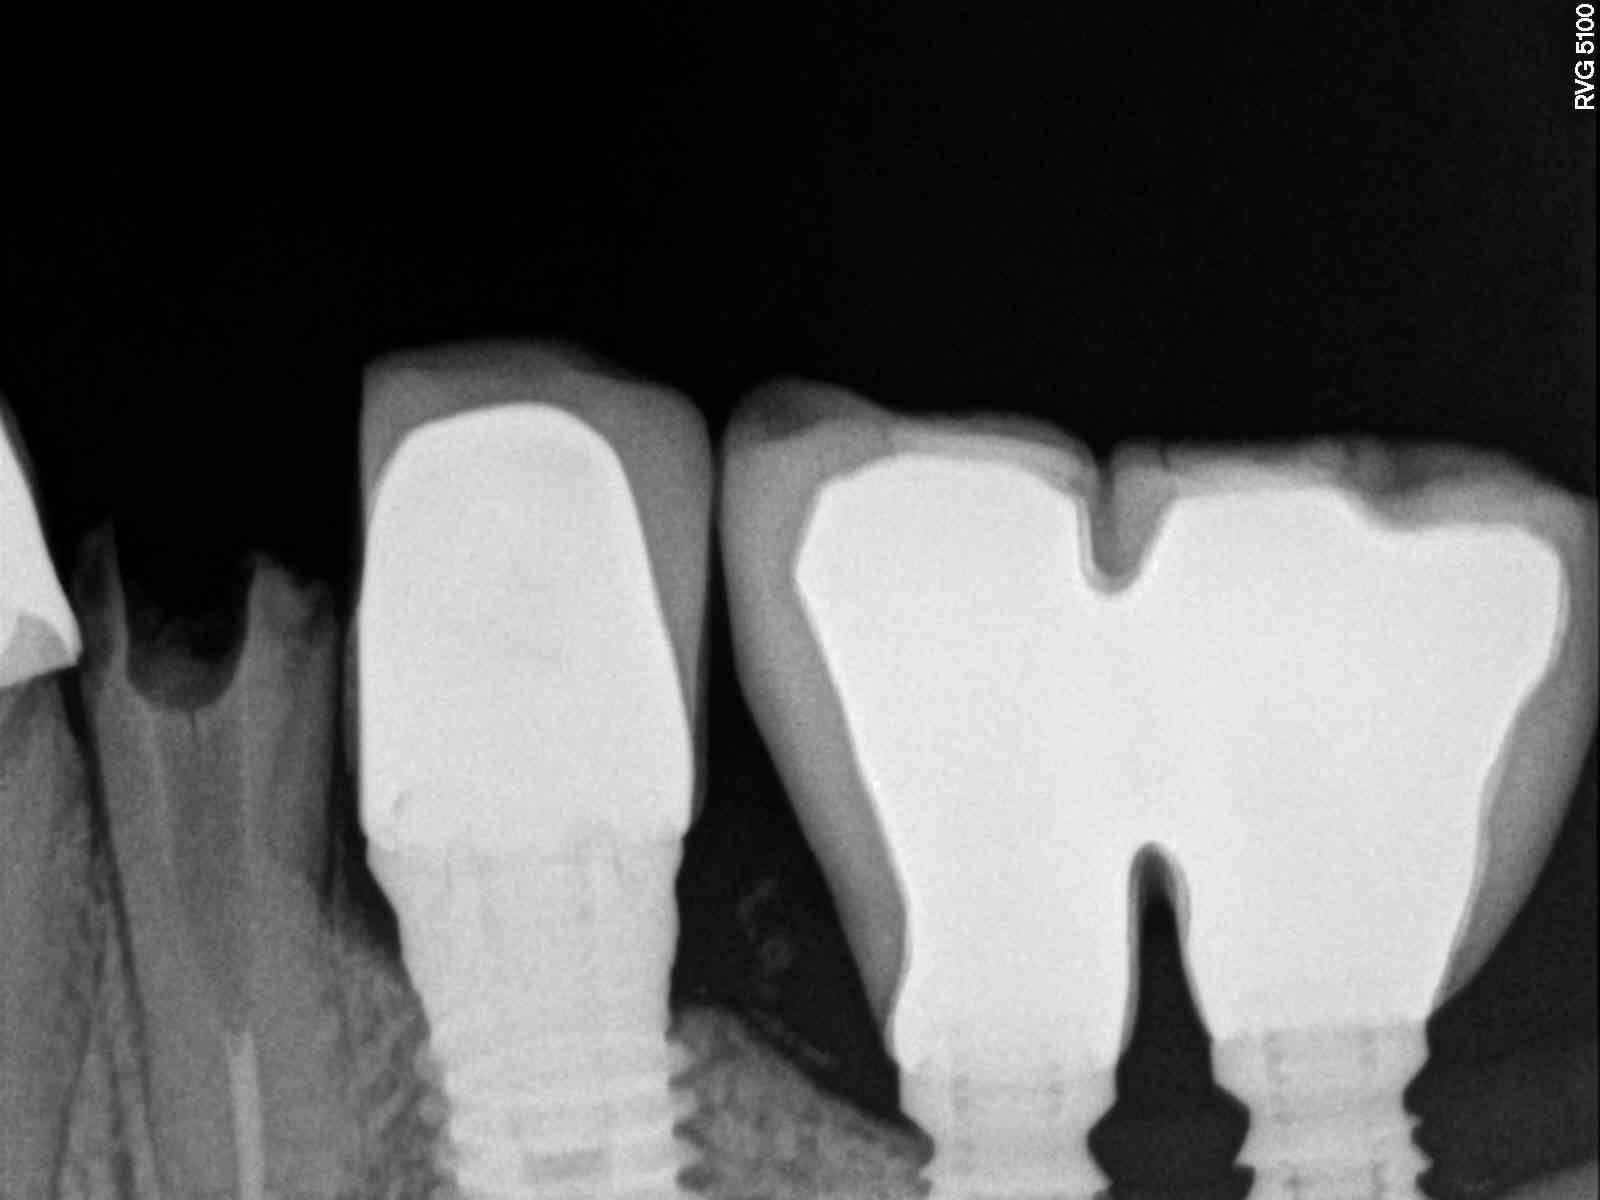

Hola 🙂 La paciente acude a consulta porque se le mueve La Corona cementada sobre el implante (conexión externa). Le pusieron ese implante hace 20 años, hay que cambiar La [...]